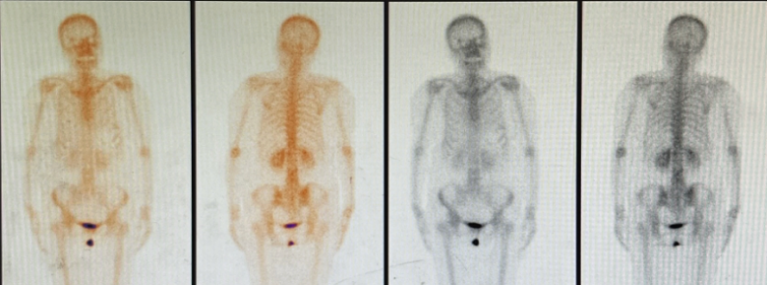

2024年12月19日复查骨ECT示:腰椎放射性分布欠均匀,见放射性分布稀疏区,以L1、2椎体为著,其余诸骨放射性分布大致均匀对称,腰椎放射性分布欠均匀,多考虑术后改变。

疗效评估:PR